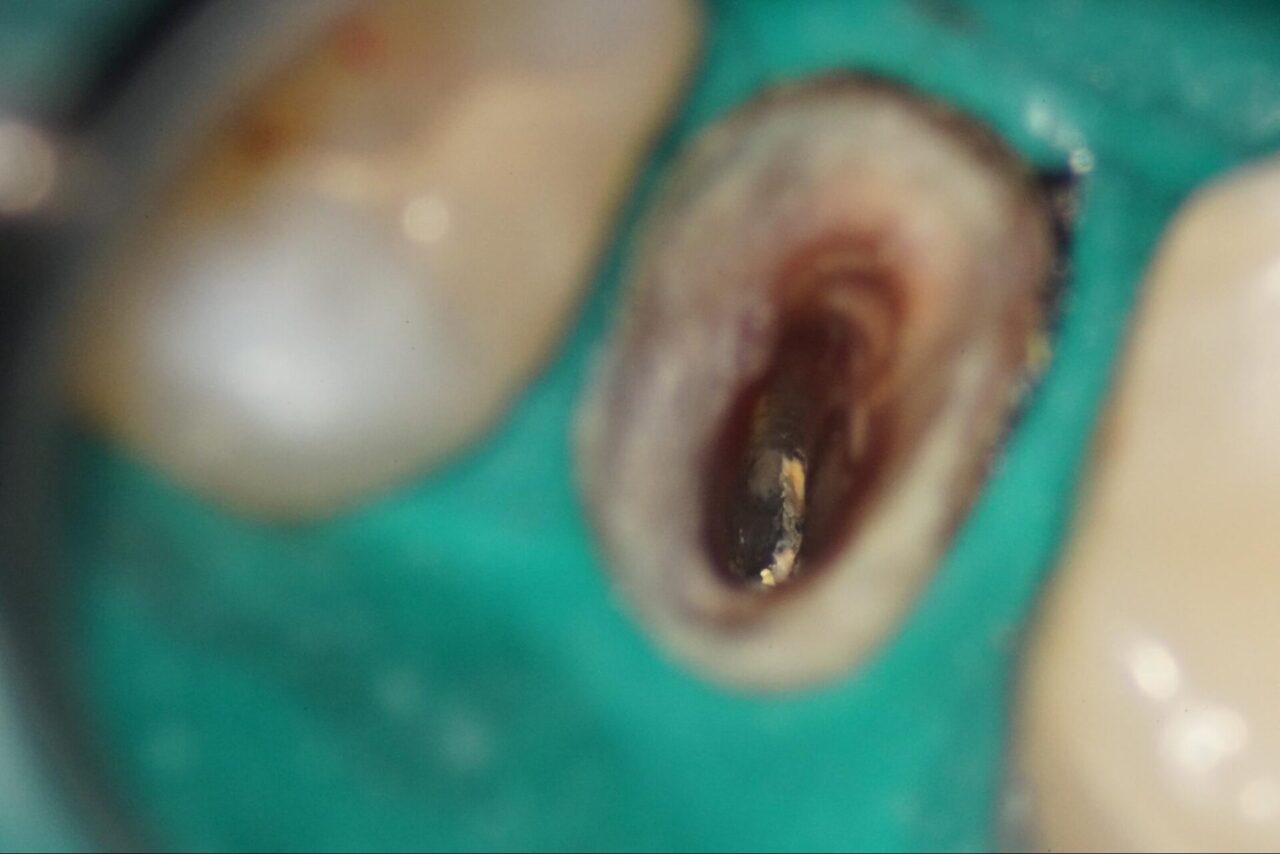

頬側根と口蓋根がつながっている事が確認できます。

以前の根管内の内容物を慎重に取り除いて行きます。

イスムと言われる根管内の複雑な形態が出て来ました。

以前の根管内にあるガッタパーチャを取り除いて行きます。頬側内壁にはクラックだと思われるスジ状のものが確認できます。